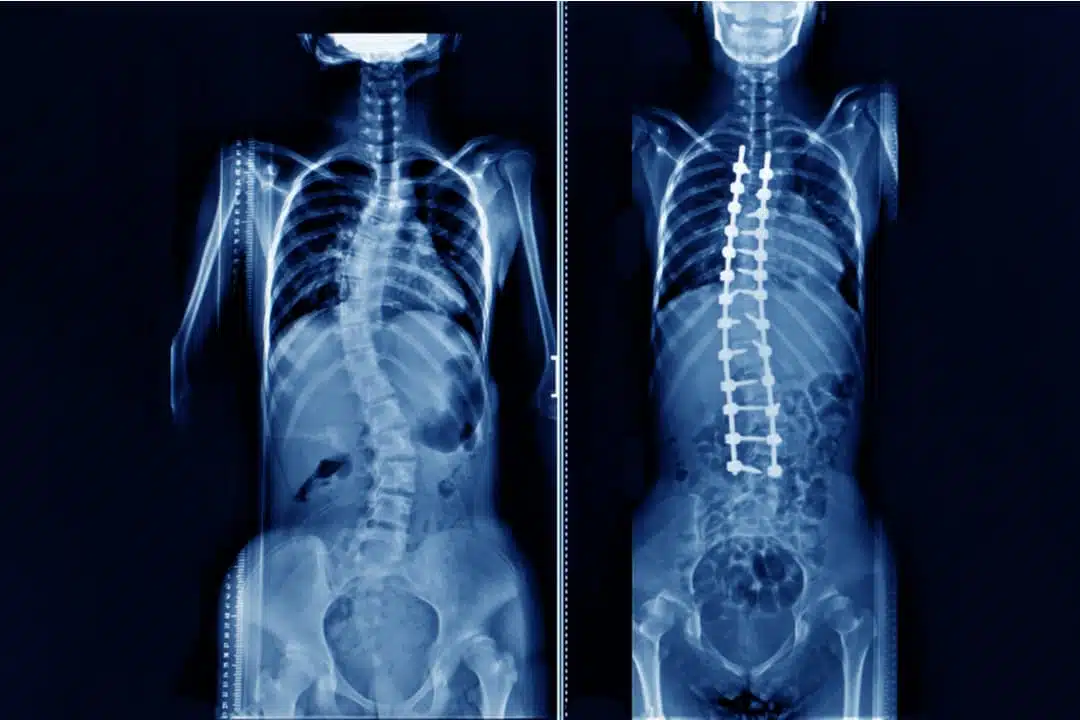

Scoliosis treatment by Surgery

When the scoliosis degree hits 40 or 50, surgery is recommended by doctors. This is true for both teens and adults. In the teen’s signs of the curve, the increase has to be present, as well. In adults, surgical treatment is recommended when the degree of the curve is 50 and the patient has nerve damage to legs or bowl or causes bladder problems. The goal of scoliosis surgery is to straighten the curve and avoid it from progressing in the future. Metal implants and rods are put in the spine to reduce or eliminate the curves. Also, the surgery keeps the spine curve straight until fusion occurs. Fusion is the knitting together of the spinal element.